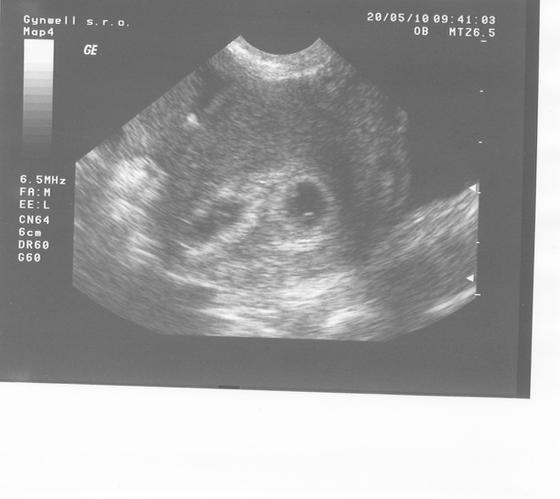

A taky se potvrdili na prvním utz 20.5. kdy jsem byla 5+2tt dva gestační váčky, s žloutkovými váčky, hrozně jsem si oddychla, když jsem viděla, že nejsou prázdná!